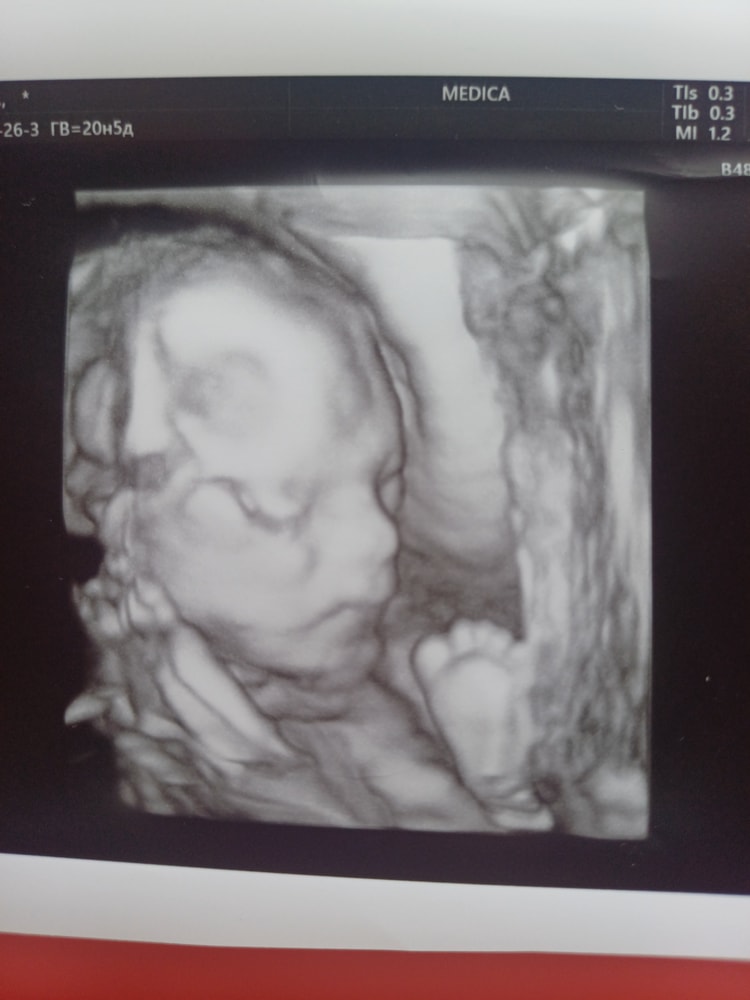

УЗИ, КТГ, доплерВчера ездили на второй скрининг.Всё отлично,человечек уже 374 гр.Всё узи держал пятки у лица,сидит на попе.(А я думаю чего так низко чувствую пиночки)Сначала совсем не хотел показываться,отвернулся к нам спиной. Узистка меня крутила и вертела по разному. Но потом дал полностью себя рассмотреть.И сестричкам помахал пяткой)Дочки с мужем зашли под конец узи посмотреть,они всю беременность мечтали именно в режиме реального времени увидеть малыша.🤩🤩🤩

С сыночком всё отлично,развивается по сроку.По месячным 20.2 недели,по узи уже 20.5.

Такой уже прям настоящий человечек💜